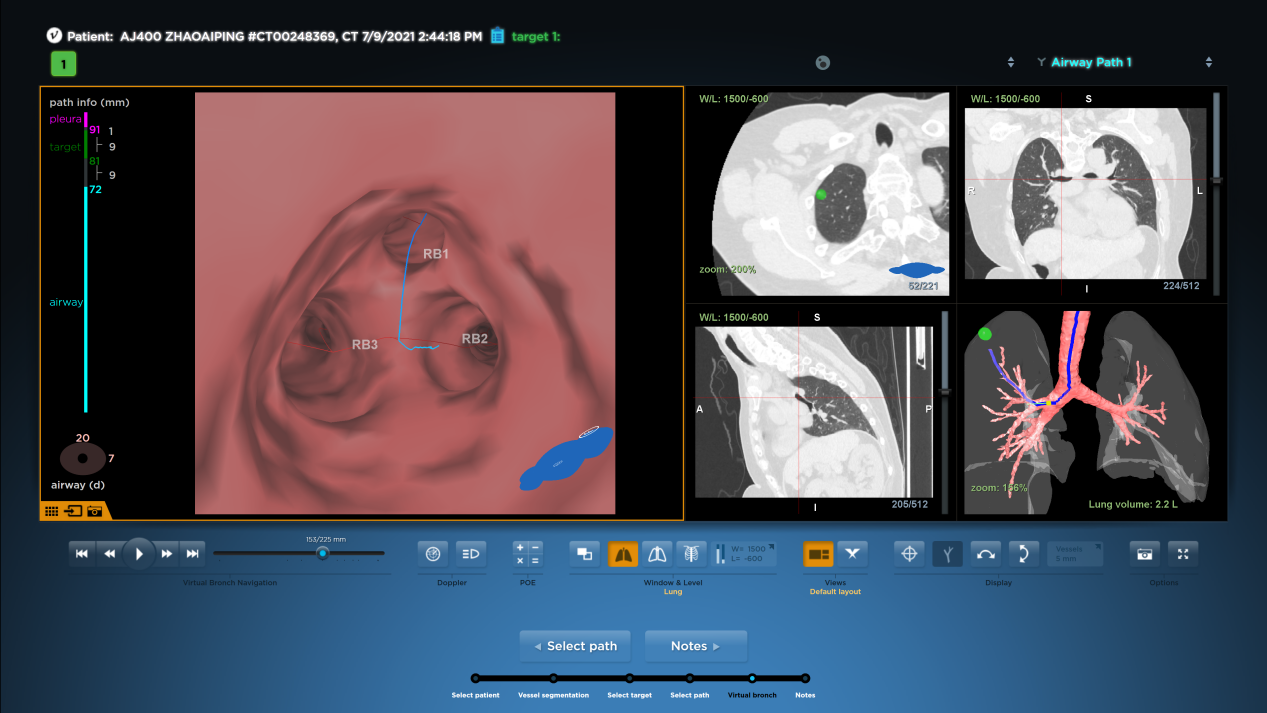

手术中,麻醉科诱导麻醉后,手术团队采用外径4.0mm的支气管镜,根据支气管导航提供的路径抵达既定位置(RB1亚亚支,约第6级气道),往前推送打药管至病灶附近胸膜处,于此处打入0.2ml美兰染色液,随后缓慢推入空气让染色液逐渐渗透至病灶附近胸膜区域。

导航路径